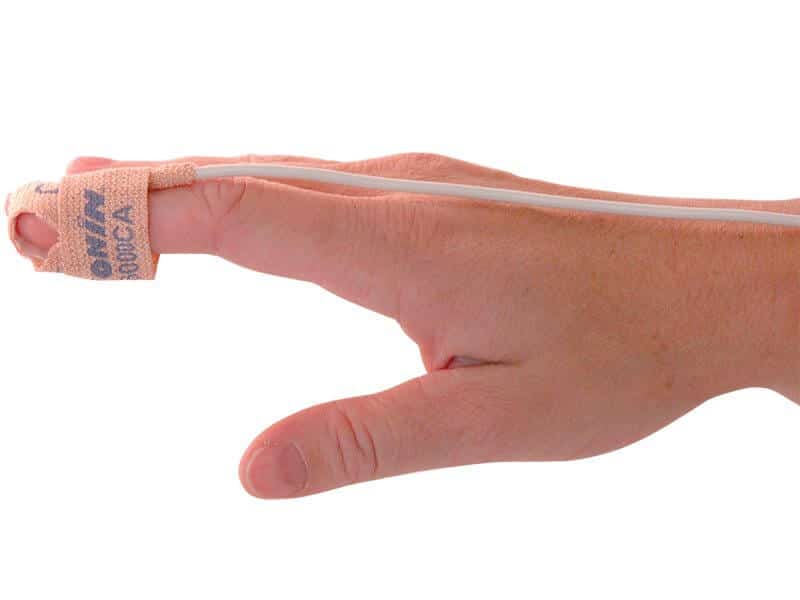

- Easy to Use Illustrated finger guide ensures easy and accurate placement by caregiver or patient

- Tear Resistant Increases the number of times the sensor can be repositioned